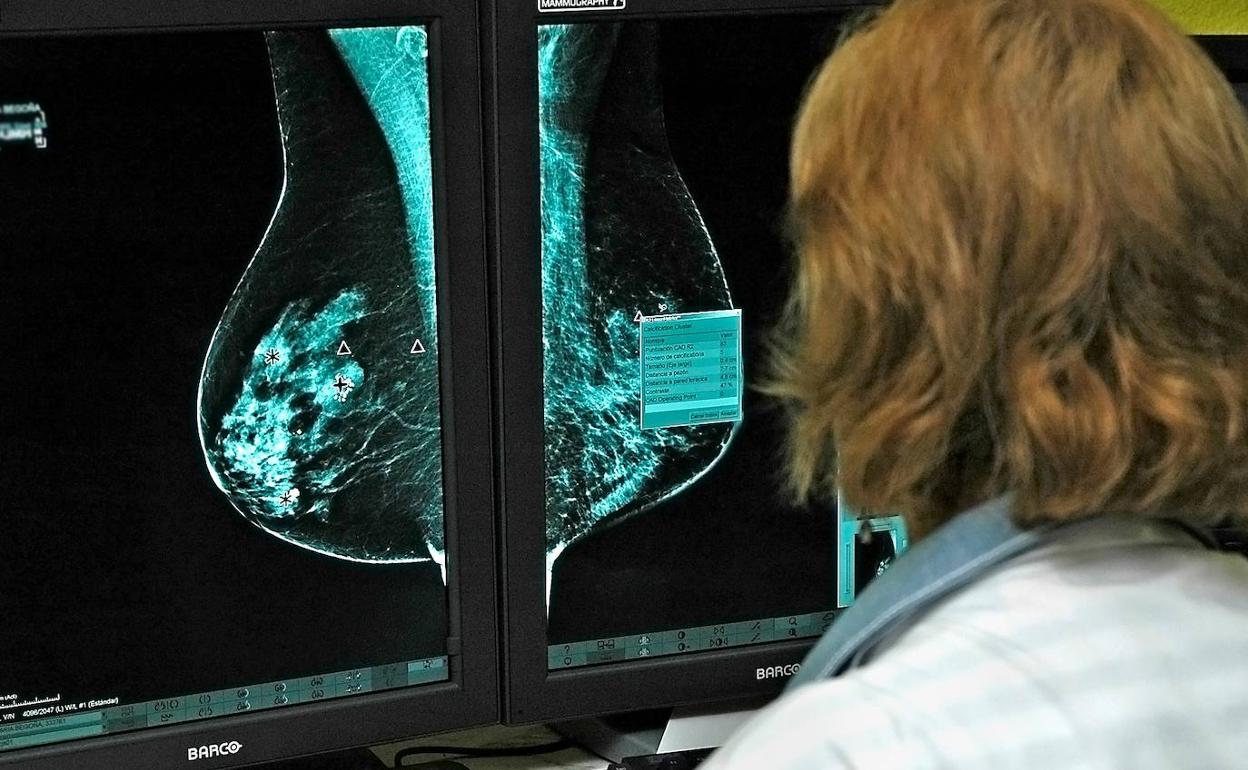

Investigadores del Laboratorio de Oncología Matemática de la Universidad de Castilla-La Mancha (UCLM) han conseguido identificar un nuevo biomarcador de imagen para pronosticar la evolución de los cánceres de mama y de pulmón a partir del desarrollo de modelos matemáticos.

El estudio ha analizado los datos de 230 pacientes oncológicos de pulmón y mama de los hospitales de Albacete y Ciudad Real con el objetivo de captar la heterogeneidad de las células tumorales. Según el profesor del Departamento de Matemáticas de la UCLM e investigador de este laboratorio, Gabriel Fernández Calvo, «a partir de imágenes médicas, los investigadores han estudiado los niveles de actividad metabólica en pacientes con tumores de pulmón y mama, o lo que es lo mismo, cómo se va reorganizando dicha actividad conforme esos tumores evolucionan».

A partir de esa compleja dinámica, se ha observado un proceso que tiene lugar en todos esos tumores, aunque a un ritmo distinto: el desplazamiento del pico máximo en la actividad metabólica hacia el borde del tumor. «Aquellos pacientes en los que a lo largo del tiempo se había producido un desplazamiento mayor del pico metabólico al borde tumoral tenían peor diagnóstico», según el doctor Fernández.

De esta forma, el nuevo biomarcador cuantifica cómo es la evolución en tumores sólidos basándose en calcular la distancia desde el centro de masas del tumor hasta el punto de máxima actividad metabólica. El trabajo ha sido publicado en la revista científica 'Proceedings of the National Academy of Sciences of the United States of America'.